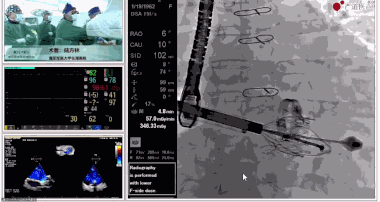

陸方林教授分享的是一例極重度三尖瓣返流的患者采用健世科技(LuX-Valve®)經(jīng)導(dǎo)管三尖瓣置換系統(tǒng)進(jìn)行的手術(shù)直播演示。此例患者為69歲女性,入院前17年行二尖瓣機(jī)械瓣置換術(shù),術(shù)后長(zhǎng)期服用華法林抗凝,既往“2型糖尿病”病史5年,“雙下肢水腫”3年。3個(gè)月前患者出現(xiàn)腹脹、雙下肢水腫,伴活動(dòng)后暈厥,伴黃疽、皮膚濕癢、牙齦出血,癥狀持續(xù)加重,遂入院治療。入院后行心臟CT、心臟超聲檢查,提示:“三尖瓣關(guān)閉不全(極重度),二尖瓣置換術(shù)后,心功能III級(jí)”。徐志云、陸方林微創(chuàng)三尖瓣置換團(tuán)隊(duì)對(duì)該患者的病情進(jìn)行了充分的評(píng)估和討論。由于患者有開(kāi)胸二尖瓣置換手術(shù)史,且病史時(shí)間長(zhǎng),同時(shí)存在相關(guān)合并癥,傳統(tǒng)外科手術(shù)風(fēng)險(xiǎn)極高(STS評(píng)分:8.315%),最終決定采用三尖瓣LuX-Valve®瓣膜系統(tǒng)對(duì)患者進(jìn)行治療。

▲瓣膜植入前右心室造影

▲瓣膜植入過(guò)程

▲瓣膜植入后釋放的過(guò)程

▲瓣膜植入后右心室造影

在手術(shù)直播中瓣膜植入過(guò)程不到10分鐘,手術(shù)獲得圓滿(mǎn)成功,充分體現(xiàn)徐志云、陸方林團(tuán)隊(duì)技術(shù)精湛,團(tuán)隊(duì)協(xié)作默契及器械的優(yōu)越性。